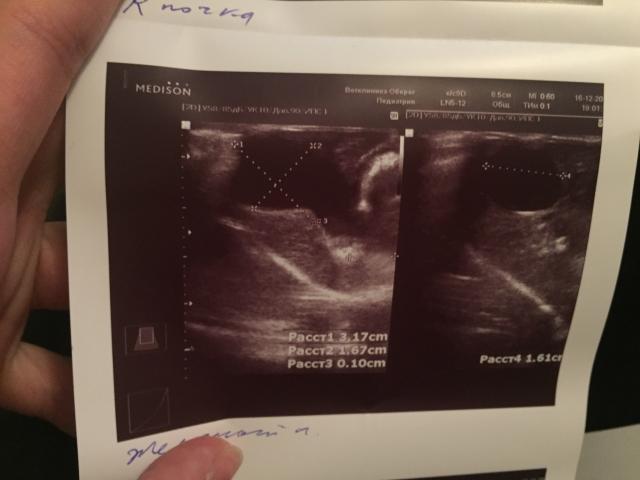

Если можно, то немного подробнее. На основании чего вам поставили такой диагноз, только на основании проведенного УЗИ? Может быть, собаке брали какие-то анализы? Если да, то выложите, пожалуйста, здесь их результаты. Если только данные УЗИ, то это разговор ни о чем (я имею ввиду панкреатит). Гастрит по данным УЗИ вообще не ставят.

Поставили диагноз на основании УЗИ , а до этого сдавали кровь

К сожалению, ничего не могу рассмотреть. Попробуйте сами прочесть описание с фото. Если сможете, сделайте снимок более качественным. Или можно снять крупнее по частям. Может быть, тогда буквы будут видны более четко.

Спасибо, фотографии четкие. Я все прочитал. Как я и думал, там и "не пахнет" никаким гастродуоденитом, а тем более, панкреатитом.